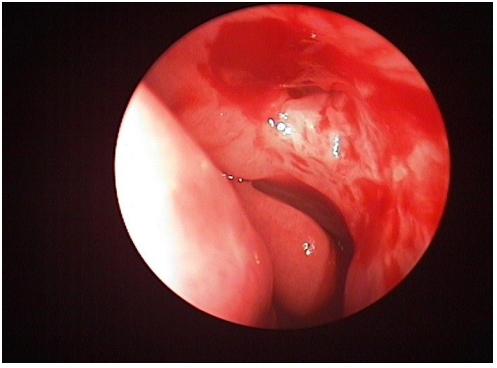

手术方法:术中沿中鼻甲前缘附着点上方约8 mm处做弧形切口,形成一约1 cm × 1.2 cm黏膜瓣,钝性分离至泪颌缝,以泪颌缝为标志,用美敦力(Medtronic,美国)IPC刨削动力系统粗磨,咬除上颌骨颈突,造一直径为1 cm大小的骨孔,暴露泪囊,经上泪小点置入探针,撑起泪囊壁,近上缘弧形切开泪囊内侧壁,形成一黏膜瓣,开放前组筛窦,剪开鼻黏膜瓣,使其贴附于泪囊造口周边骨面上,泪囊瓣与鼻黏膜瓣之间无需缝合,周围填充沾有妥布霉素地塞米松眼膏眼药膏的吸收性明胶海绵[14],见瘘口形成良好,检查无出血。合并泪总管、泪小管狭窄时植入泪道引流管,分别自上下泪小点插入引流管,自鼻腔内勾出并打结。术中同期处理鼻腔、鼻窦病变。手术均由同一位经验丰富技术熟练的医师完成。术后随访及处理:术后1个月内用药为布地奈德鼻喷雾剂2次/天,0.1%氟米龙滴眼液滴术眼3次/天。术后每2周复查1次鼻内镜检查,复查3次后根据恢复情况确定随访间隔时间,所有患者随访时间均大于6个月。随访内容包括以下3项:1)鼻内镜下鼻腔处理,清除鼻腔内血痂、分泌物、黏膜粘连及增生的肉芽组织,如发现肉芽组织增生(图1、3),则用枪镊夹除肉芽组织,造瘘口周围涂妥布霉素地塞米松眼膏,其中物理清除联合TA组予鼻黏膜下注射TA注射液(40 mg/mL)0.3 ~ 0.5 mL,保证注射面积覆盖80%肉芽组织创面(图2、4),间隔2周复查,如发现肉芽复发则再次清除并注射TA。2)泪道冲洗,分别经上下泪小点以地塞米松注射液和生理盐水冲洗泪道。3)如术中联合植入泪道引流管,一般于3个月后拔除。

图1 造瘘口肉芽组织增生

Figure 1 Granuloma formation in the ostium